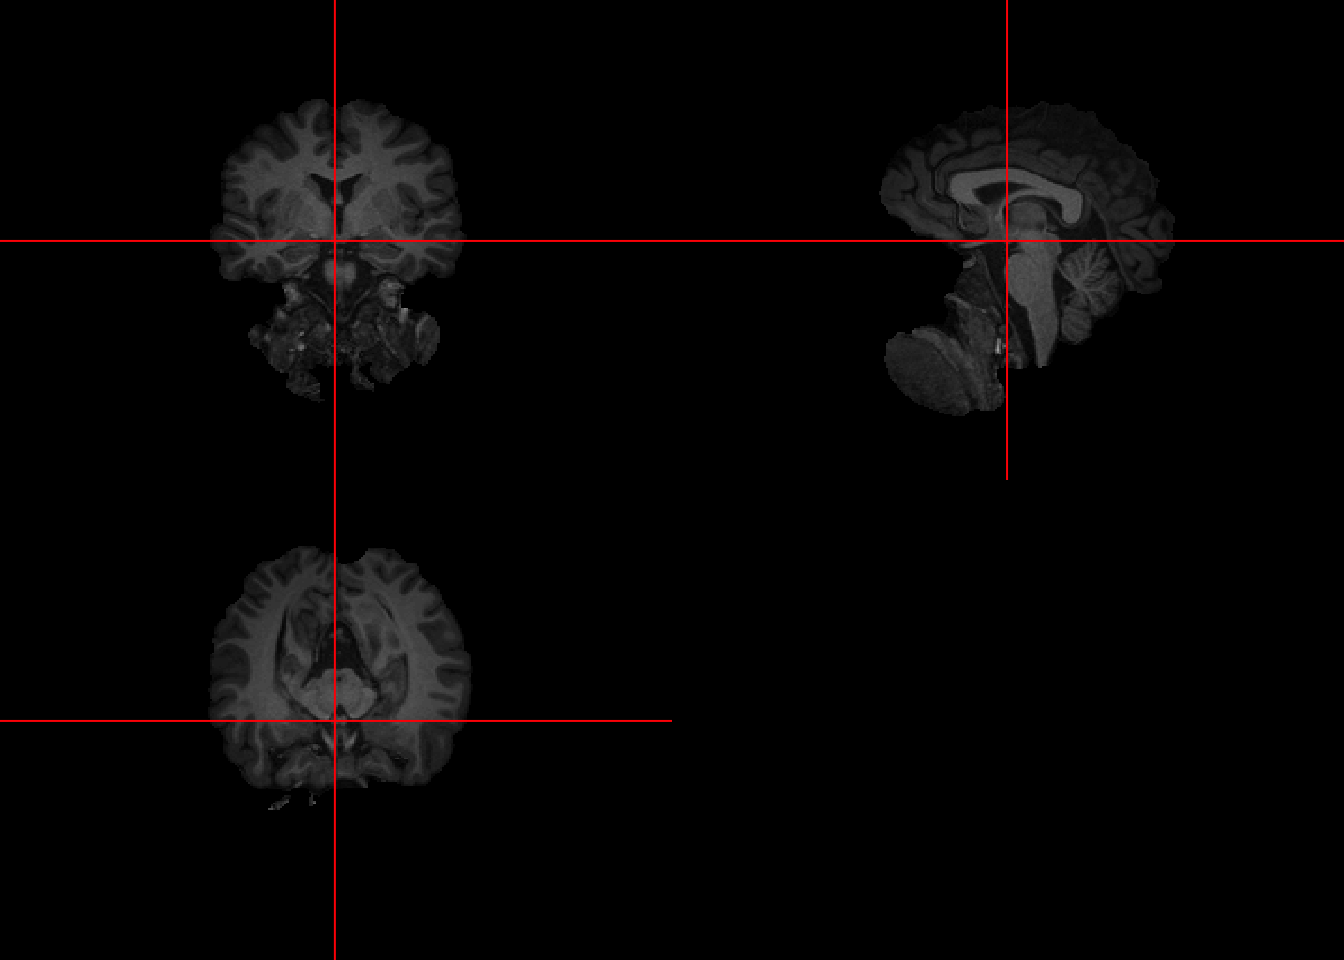

mask = readNIfTI(maskfpath, reorient=FALSE) 4.2 Visualization

This brain was collected with a bigger FOV than the previous scans. Thus a lot of body parts other than brain are shown.